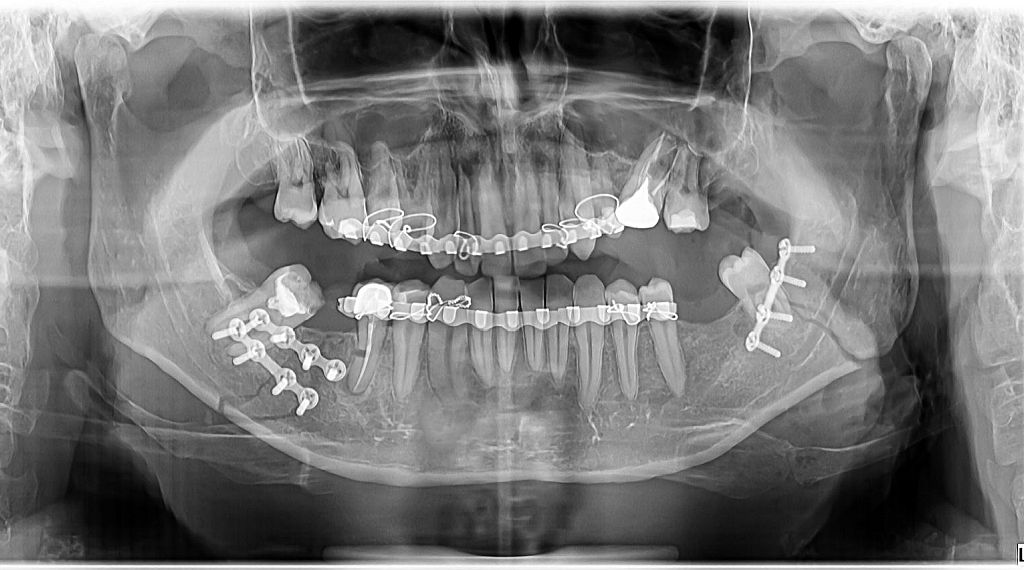

Victima a suferit răni grave, având maxilarul rupt și necesitând implantarea a 12 șuruburi. Medicii i-au acordat 60 de zile de îngrijiri medicale.